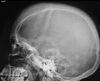

• hair on end appearance of skull

• Erlenmeyer flask deformity

What causes the hair on end appearance seen in thalassemia?

A

Marrow hyperplasia

(inner/outer table space fills w/ red marrow to ^RBCs, spreading inner & outer tables)